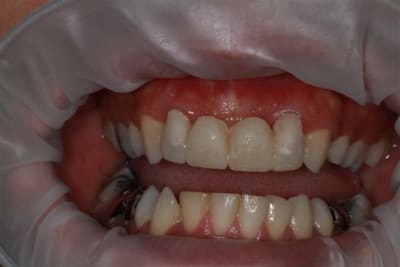

la suite

reconstitution, taille pour empreinte et provisoire (pas beau mais il sera remplacé)